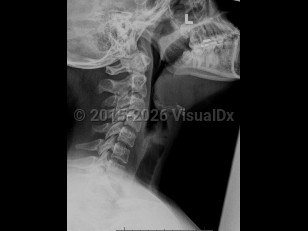

EpiglottitisEpiglottitis